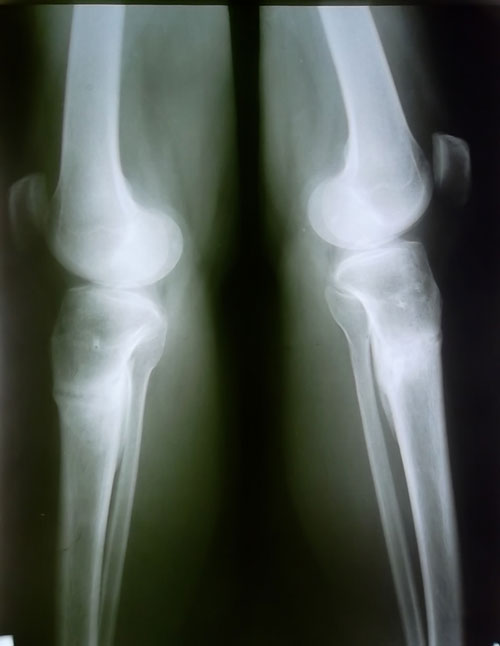

рентген в 1,5 месяца после снятия аппаратов.

Сращение отличное, живи без ограничений! d6c695c748.gif